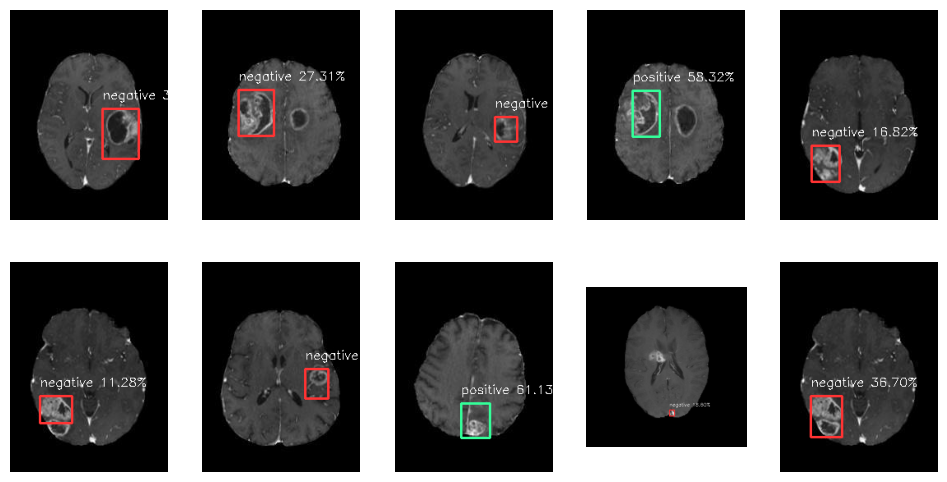

4주차 실습: Selective Search와 Binary Classification을 통한 간단한 R-CNN 구현(MRI 사진을 활용하여 종양의 위치와 양성/음성 여부를 판단)

>> 모델 학습 결과!